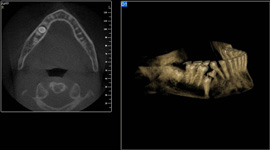

3D DVT - NewTom

Je speciální zubní digitální tříprostorový tomograf (3D), který umožňuje na základě jediného snímkování vytvořit všechny typy RTG zobrazení, které jsou pro lékaře potřebné. Díky používané technologii tzv. „kuželového paprsku“ a speciálním senzorům je výrazně zmenšená dávka záření - o více jak 80% proti klasickému CT vyšetření. To je významné zejména u dětí. Pomocí tohoto přístroje je možné zjisti skutečnou situaci v čelistních kostech pacienta tedy množství kosti - můžeme změřit skutečnou šířku i výšku kosti, i kvalitu kosti (hustotu) v místě uvažované implantace. 3D (tříprostorové) zobrazení umožňuje zvýšit prostorovou představu operatéra ještě před vlastní operací a zároveň pacientovi lépe objasnit a ukázat oblast plánovaného zavedení implantátu.

Pacient „neumí číst“ RTG snímky, ale díky 3D zobrazení vidí „svoji skutečnou čelist“ - např. jak je nízká či úzká, vidí průběh nervu nebo velikost čelistní dutiny, což mu umožní i pochopení nutnosti v některých případech provést pomocné zákroky ještě před vlastním zavedením implantátu (viz. kostní štěp, sinus lift, kostní granulát...).

Vyšetření pomocí tohoto přístroje používáme i ve stomatochirurgii (zlomeniny čelistí, zuby moudrosti, cysty, onemocnění čelistního kloubu), ortodoncii (retinované zuby, nadpočetné zuby), parodontologii atd.